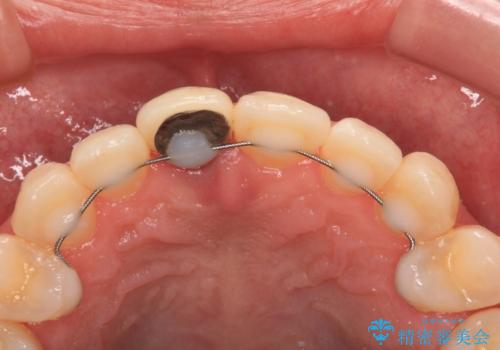

- 以前他院にて保険診療で治療した前歯のやり替え希望の患者様です。

被せものと土台の境目が段差になっています。

審美的にも清掃性の観点からも理想的とは言えない状態です。